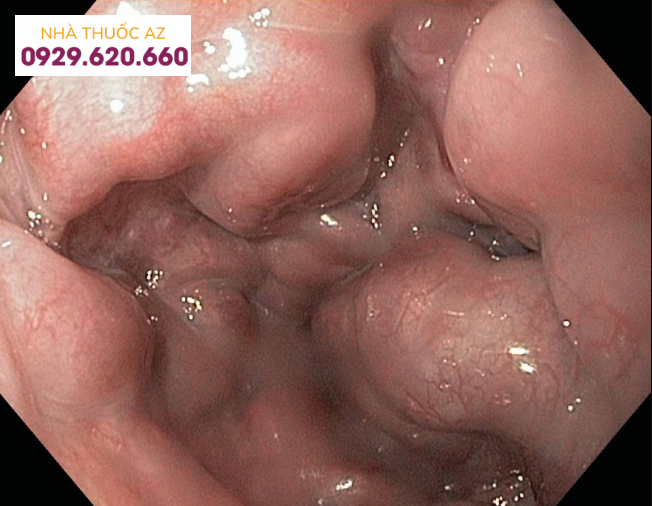

Giãn tĩnh mạch: Nguyên nhân là do tăng huyết áp kịch phát làm các mạch máu bên trong cơ thể bị mỏng ra. Nếu mạch máu quá mỏng có thể dẫn đến vỡ. Vỡ mạch máu ở thực quản và dạ dày thì người bệnh sẽ bị chảy máu nghiêm trọng.

Giãn tĩnh mạch thực quản dạ dày